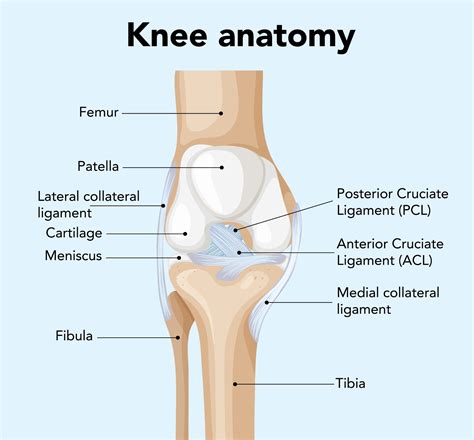

Understanding the Tibia Bone

The tibia, commonly known as the shinbone, is the larger of the two bones in the lower leg. It plays a crucial role in supporting the body’s weight and facilitating movement. The tibia is connected to the knee joint at the top and the ankle joint at the bottom, making it a vital component of the leg’s structure and function.